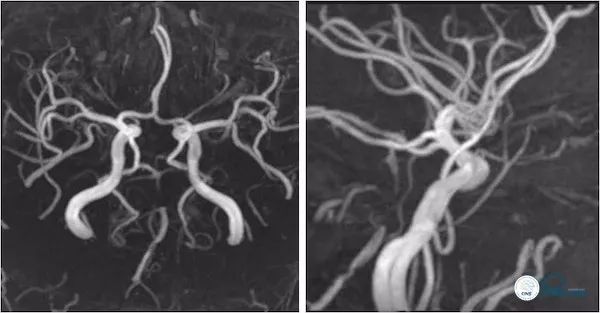

头颅MRA:右椎动脉V4段及基底动脉狭窄(图3)。

图3

头颈部CTA:左椎动脉闭塞,右椎动脉V4段狭窄,基底动脉局限性狭窄,双侧后交通动脉开放(图4)。

图4